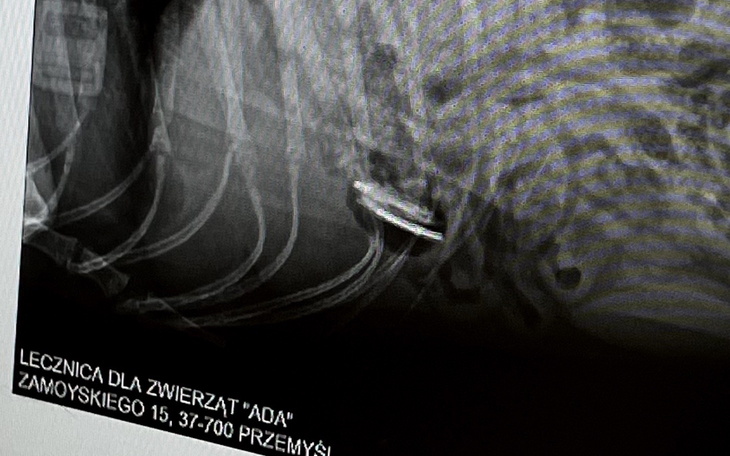

Emergency. Jędruś nagle źle się poczuł. Opiekunowie zareagowali natychmiast i dzięki temu szybko trafił do lekarza. Badanie ujawniło dramatyczną prawdę. W jego brzuchu utknęło ciało obce. Każda godzina zmniejsza jego szanse.